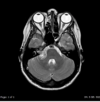

State where this stroke has occured

Right MCA